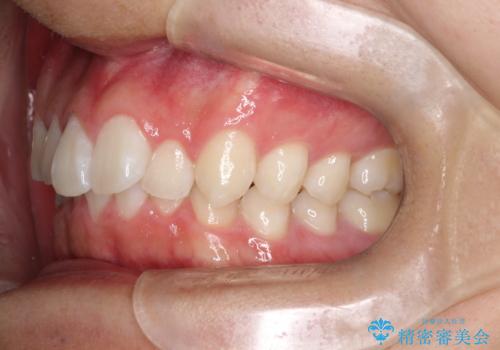

- 歯のデコボコと過蓋咬合を主訴に来院された患者様です。

アーチの拡大とIPRを行い非抜歯で治療を行いました。

歯を抜かずに叢生(デコボコ歯列)と過蓋咬合を改善する事が出来ました。

インビザラインによる治療でも十分に美しい歯並びを実現でき、患者様にも大変ご満足いただけました。